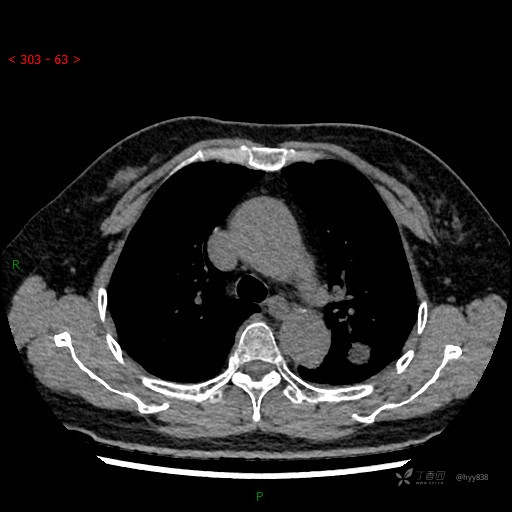

静脉期

各期CT值:28hu、58hu、69hu